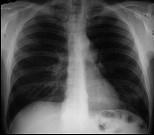

问题 47岁,男,腹泻、体重下降,伴有重症肌无力,请结合胸片和CT图,选择最可能的诊断 ( )

选项 A.胸腺增生 B.胸腺瘤 C.淋巴瘤 D.纵隔血肿 E.错构瘤

答案 B